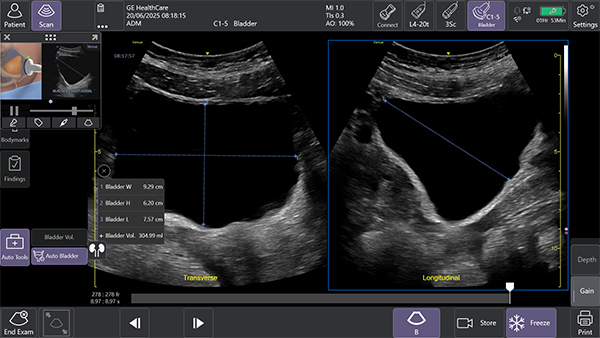

2. AIツールAuto Bladder Volume(オートブラッダーボリューム)で膀胱評価を効率化

AIを用いて開発されたAuto Bladder Volumeは,膀胱の容積を半自動で計測するツール。横断像および縦断像の2方向の画像から,AIが自動的に膀胱形状を認識し容積を算出するため,再現性の高い評価が可能になる。

救急外来や集中治療室,手術後,病棟など様々な場面での活用が想定され,侵襲的な処置を行う事なく迅速かつ効率的な膀胱容積評価が可能となる。

Auto Bladder Volumeにより2断面から半自動的に膀胱容積を計算